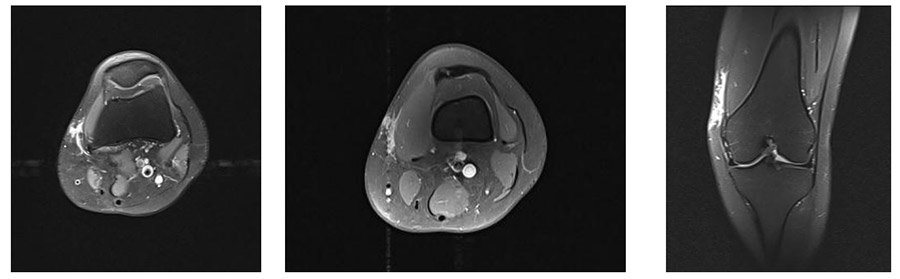

Ameliyat Öncesi: MR’da ilk ameliyat sonrası kalıntı tümör dokusu görülmekte